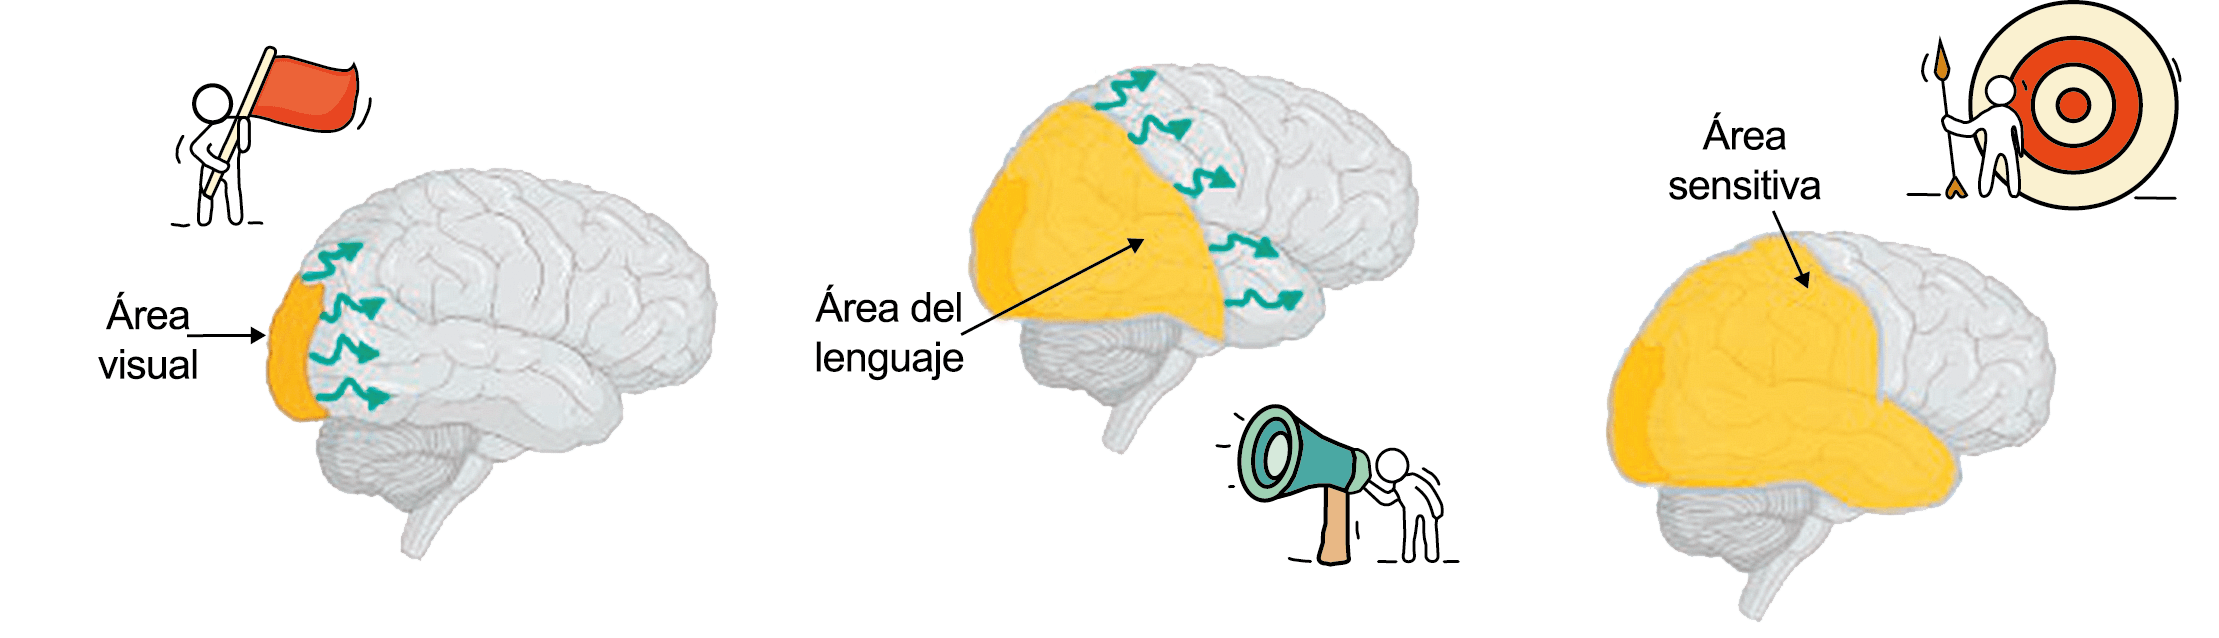

Se cree que una onda transitoria de despolarización neuronal de la corteza (Figura 9), la depresión de propagación cortical (CSD), es el mecanismo cerebral fisiopatológico subyacente al fenómeno clínico del aura de la migraña. Leão(21) estableció un mecanismo subyacente hipotético. Luego de haber estimulado eléctricamente la corteza de conejo y encontrar una depresión EEG que se propagaba a una velocidad similar de 3 mm/min centrífugamente desde el sitio de estimulación sugirió que podría ser la base del aura migrañosa. Esta hipótesis está fundamentada en la correlación entre las características neurofisiológicas de una CSD, su propagación retinotópica en la corteza visual y las características y dinámicas de los déficits visuales(14, 15) y en las observaciones indirectas derivadas de los estudios de imágenes que respaldan aún más este concepto(16) Sin embargo, sobre la base de la comprensión actual de la migraña, es poco probable que la CSD esté involucrada en el inicio del síndrome completo de la migraña(17).

El dolor de cabeza asociado con un ataque de migraña, puede incluir la región frontal, temporal, parietal, occipital y cervical alta, es consecuencia de la activación del sistema trigeminovascular. (Figura 10)

La anatomía del sistema trigéminovascular ha sido bien descrita durante los últimos 70 años y esto ha ayudado a comprender la fisiopatología de la migraña y la distribución de su dolor. Se sabe que el cerebro es en gran parte insensible, pero un rico plexo de fibras nerviosas nociceptivas que se originan en el ganglio del trigémino inervan los vasos sanguí- neos de la piamadre, la aracnoides y la duramadre, incluidos el seno sagital superior y la arteria meníngea media, así como las grandes arterias cerebrales. (Figura 11) (23)

La inervación nociceptiva de la vasculatura intracraneal y las meninges incluye proyecciones axonales no mielinizadas (fibras C) y mielinizadas delgadas (fibras Aδ), principalmente a través de la división oftálmica (V1) del nervio trigémino, pero también, en menor medida, a través del nervio maxilar. (V2) y divisiones mandibulares (V3). También hay inervación neuronal de la duramadre desde los ganglios de la raíz dorsal cervical (24) (Figura 12).

Hay una proyección aferente central desde el ganglio del trigémino que ingresa a la médula caudal del tronco encefálico, a través del tracto del trigémino, que termina en el núcleo espinal del trigémino caudalis (TNC), así como la médula espinal cervical superior (C1–C2). (Figura 16)

Las fibras nociceptivas Aδ y C terminan predominantemente en las láminas superficiales, I y IIo, así como en las láminas más profundas V–VI del TNC y extensión cervical. La estimulación de la vasculatura dural en modelos animales, incluidos los senos transverso y sagital superior y la arteria meníngea media, da como resultado la activación de las neuronas en las regiones TNC, C1 y C2 de la médula espinal cervical, conocidas en conjunto como el complejo trigeminocervical (TCC).

Estos datos sugieren que el núcleo del trigémino se extiende hasta el asta dorsal de la región cervical superior en un continuo funcional que incluye la extensión cervical, ello explica la distribución de la percepción del dolor en la migraña sobre las regiones frontal y temporal, además de la participación de parietal, occipital y regiones cervicales superiores(27).

Por lo tanto, se cree que la naturaleza intensa y pulsátil del dolor en la migraña es el resultado de la activación, o la percepción de activación, de estas entradas nociceptivas de las estructuras intracraneales y extracraneales, que convergen y se transmiten a través del TCC. (Figura 17)